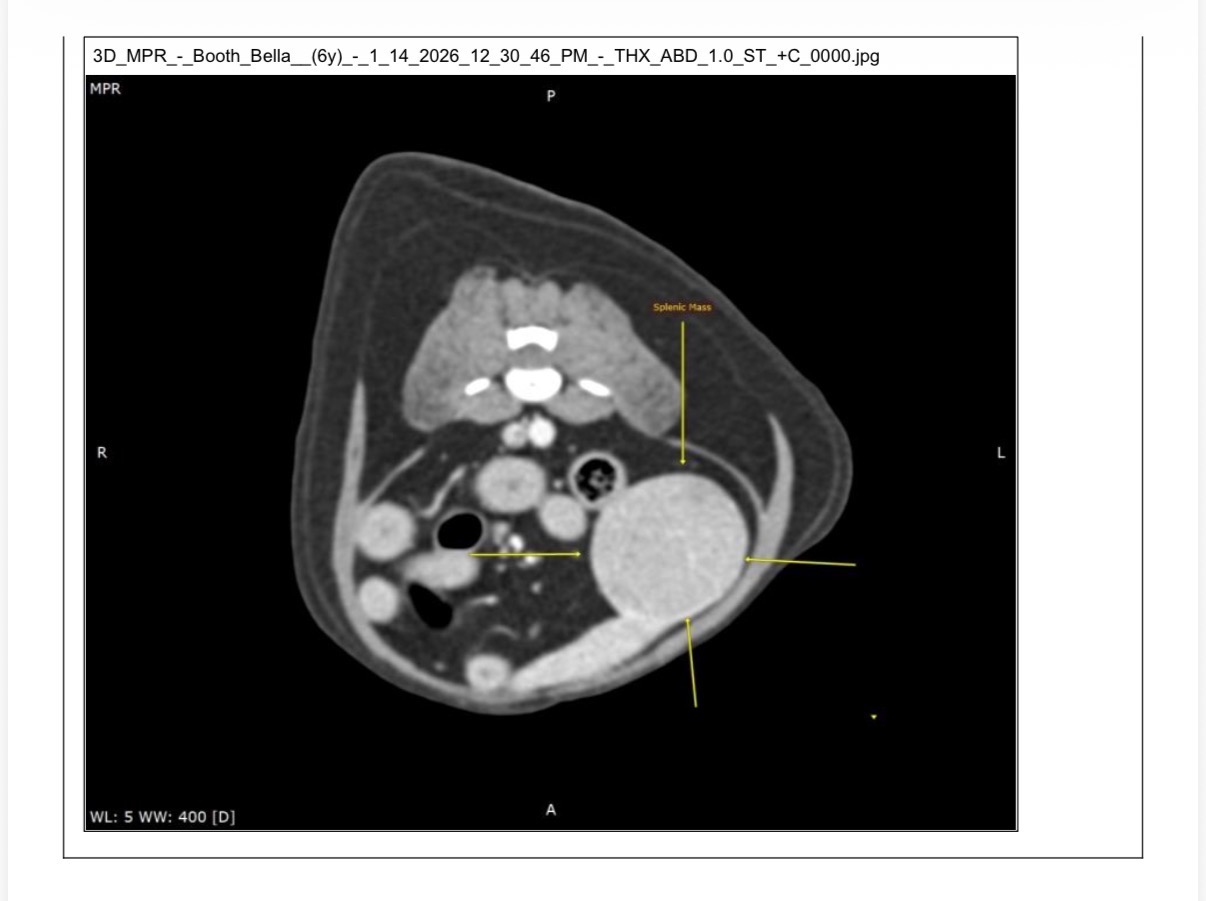

Recently, Bella became very ill. After extensive & expensive imaging, we received devastating news: she has a tennis ball–sized tumor on her spleen. She is in significant pain and without surgery she will not survive.

The only chance to save her life is surgical intervention immediately to prevent the large tumor from rupturing her spleen which would cause her to bleed internally. This is something she would not survive from.